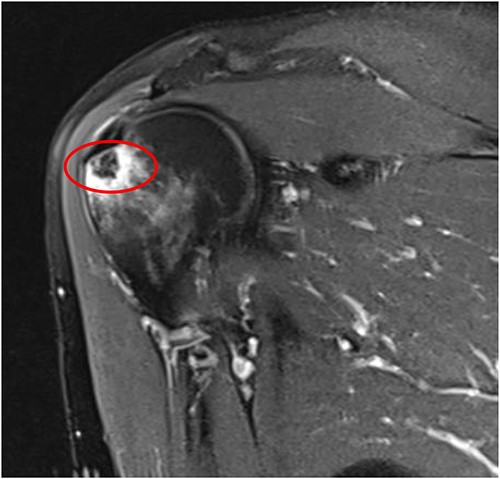

An MRI of the right shoulder showed calcifications over the supraspinatus tendon with an intraosseous lesion mimicking an aggressive or benign skeletal neoplasm (see Figs 2 and 3).

Axial T2 image of right shoulder showing hypointense lesion; note: the red circle indicates the intraosseous extension of calcified deposits originating from calcified supraspinatus tendon, with surrounding marrow edema.